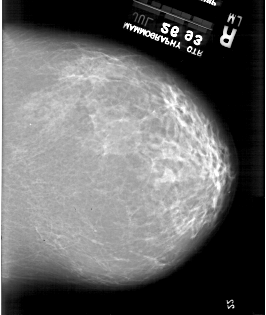

A_1918_1.RIGHT_CC

RIGHT_CC LINES 5656 PIXELS_PER_LINE 4771 BITS_PER_PIXEL 12 RESOLUTION 43.5 NON_OVERLAY